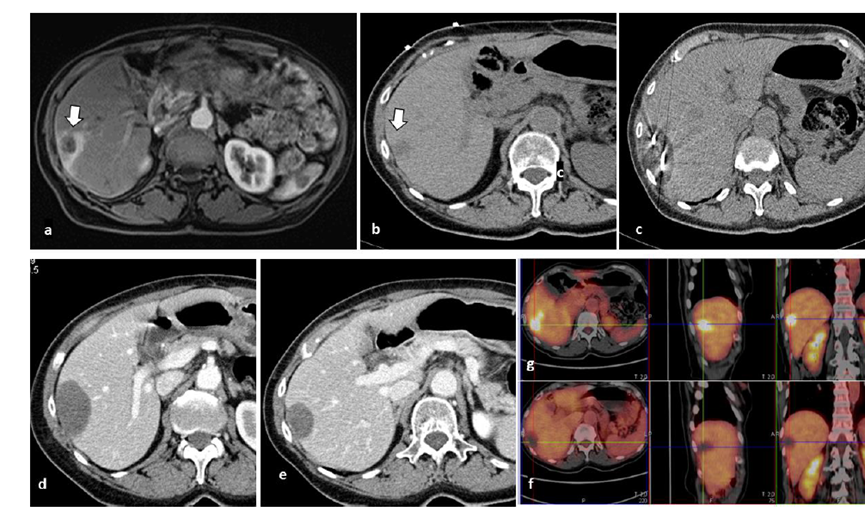

冷冻消融肝包膜下肝细胞癌

(A)动脉期CT图像显示有一个包膜下结节(箭头)。

(B)门静脉期CT图像显示病灶区(箭头)。

(C) 在手术过程中的CT显示一个冷冻探针位于病灶内。

(D)消融后,术后1个月影像CT显示完全消融。

胆囊附近转移灶(来自子宫颈癌)的冷冻消融术

(A)门静脉期 CT 图像显示胆囊附近有病变(箭头)。

(B) PET-CT 图像显示病变处(箭头)。

(C) 手术过程中CT 显示冷冻探针位于病灶内。

(D)消融手术后 1 个月CT 显示完全消融。